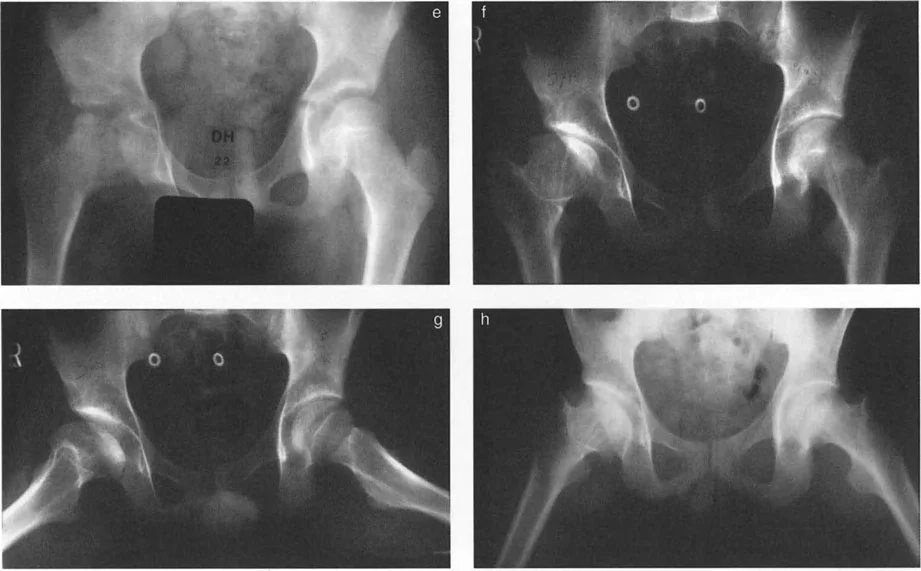

- خلل التنسج النمائي للورك (DDH): يحدث عندما لا يتطور مفصل الورك بشكل صحيح عند الرضع والأطفال، مما يؤدي إلى عدم استقرار المفصل أو خلع جزئي أو كلي.

- انزلاق مشاش رأس الفخذ (SCFE): حالة شائعة تحدث غالبًا في مرحلة المراهقة، حيث ينزلق رأس عظم الفخذ عن عنقه عند صفيحة النمو.

- الأشعة السينية التقليدية: تُظهر صور الأشعة السينية الأمامية الخلفية (AP) والجانبية (Lateral) للورك العظام الرئيسية وتساعد في الكشف عن التشوهات الواضحة.

- صور الأشعة الجانبية عبر الطاولة (Cross-table lateral view): تُعد هذه الصورة حاسمة لتقييم الزاوية الأمامية لعنق الفخذ (ANSA) وتحديد التشوهات في المستوى السهمي. يُشدد الأستاذ الدكتور محمد هطيف على ضرورة الحصول على هذه الصورة بشكل صحيح، بحيث تكون موجهة بالنسبة لـ "المنظر الأمامي الحقيقي للورك" وليس الركبة، لتجنب ما يُسمى "فخ الالتواء".

- التصوير بالرنين المغناطيسي (MRI): يُوفر صورًا تفصيلية للأنسجة الرخوة مثل الأربطة، الأوتار، الغضاريف، ويُساعد في الكشف عن النخر اللاوعائي أو أمراض داخل المفصل.

- الأشعة المقطعية (CT Scan): تُوفر صورًا ثلاثية الأبعاد للعظام، وهي ضرورية لتقييم التشوهات المعقدة والالتواءات وتخطيط الجراحة بدقة فائقة.